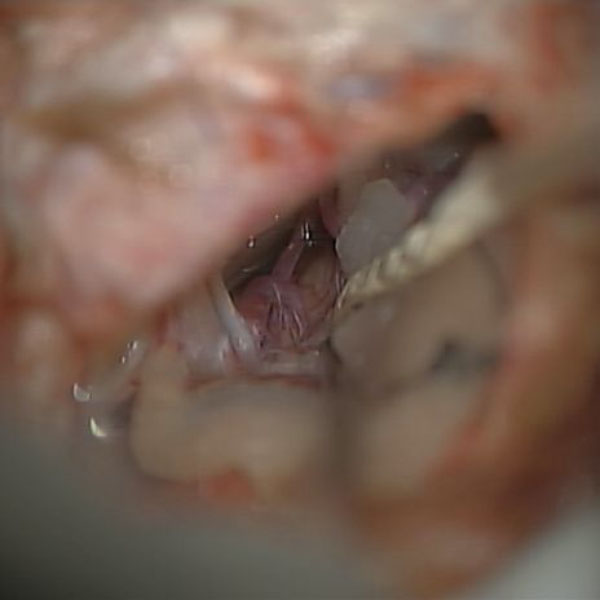

手術中

処置前

処置後